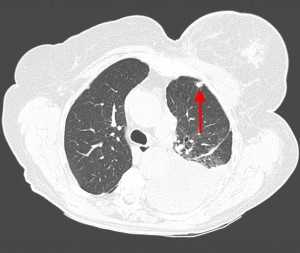

Метастазы в легких на КТ

Гематогенные метастатические узлы в легких на КТ имеют довольно четко очерченные и ровные контуры. Нечеткие, расплывчатые или лучистые контуры наблюдаются в том случае, если есть инвазивный рост в окружающую легочную ткань. Локализуются преимущественно в нижних, периферических отделах легких, хаотично, без очевидной связи с бронхами и крупными легочными сосудами.

Вторичные узлы гематогенного характера чаще всего имеют ровные края, четкие контуры и однородную структуру. Возможны изменения структуры опухоли вследствие кровоизлияния в паренхиму, обызвествлений, некроза центральной части узла, а также рубцов. Края узла могут стать нечеткими, расплывчатыми, если опухоль провоцирует отек легочной паренхимы, либо «лучистыми», если имеет место опухолевый лимфангиит.

Гематогенные метастазы наиболее часто локализуются в периферических отделах легких, вдали от крупных сосудисто-бронхиальных пучков, вблизи плевральной оболочки. При множественных поражениях гематогенного характера наблюдается тенденция к увеличению количества очагов в направлении «сверху-вниз». Чаще гематогенные метастазы расположены хаотично, вне четкой связи с бронхами и видимыми легочными сосудами. Практически не бывает такого, чтобы гематогенные вторичные узлы находились только с одной стороны, или занимали только одну долю или сегмент. При наличии такого распределения в первую очередь нужно думать о туберкулезе (верхние доли), множественных абсцессах и т. д.